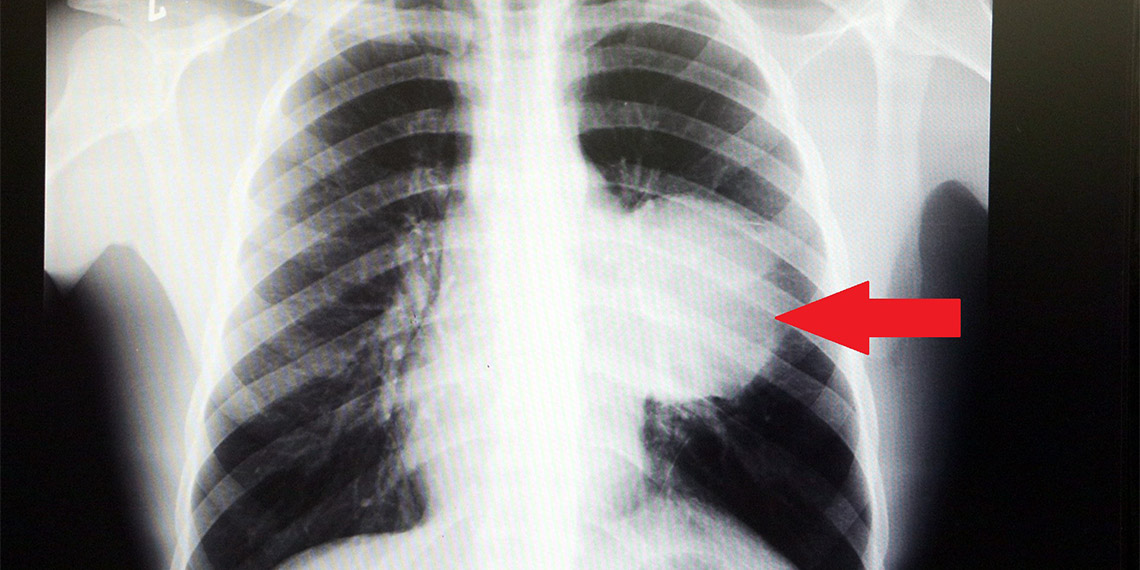

İstanbul’da yaşayan Burak Aktaş (21), Ağustos ayında halsizlik ve nefes darlığı şikayeti ile doktora gitti. Sol göğüs boşluğunda portakal büyüklüğünde bir kitle tespit edildi. İki seans kemoterapi gördü ama tedaviye rağmen tümör 2 ay içinde 8-10 kat büyüyerek karpuz boyutuna ulaştı. Kalbini göğüs boşluğunda 12 santimetre sağa iten, sol akciğerini neredeyse tamamen ezen dev tümör, Koşuyolu Yüksek İhtisas Eğitim ve Araştırma Hastanesi Göğüs Cerrahisi ve Kalp Damar Cerrahisi ekiplerinin beraber katıldığı büyük bir operasyonla başarıyla çıkarıldı. Bu kadar hızlı büyüyen kitle karşısında doktorları da şaşırdı.

Sol akciğerinin yüzde seksenini kağıt gibi ezen, kalbini göğüs duvarında 12 santim sağa kaydıran ve hem kalbe hem beyne giden ana damarlara baskı yapan 6.5 kilo ağırlığındaki dev tümör, Koşuyolu Yüksek İhtisas Eğitim ve Araştırma Hastanesi Göğüs ve Kalp Damar Cerrahisi ekiplerinin birlikte girdiği operasyonla başarılı şekilde çıkarıldı. Operasyon sırasında Aktaş’ın kalbi normal yerine çekildi, sol akciğerin üst lobu alındı, ezilen alt lobu ise anestezi ekipleri tarafından pozitif basınçla yeniden şişirildi. Ameliyatı gerçekleştiren ekipten Prof. Dr. Erdal Taşçı, Aktaş’ın göğüs boşluğunun neredeyse tamamını kaplayan 6,5 kiloluk tümörün teratom (eski Yunancada ‘canavar tümör’) türlerinden biri olduğunu ve embriyonik hücrelerden kaynaklandığını kaydetti.

Göğüs boşluğunda kemik kafesi içinde olduğu için, itebileceği iki organ var; biri kalp, diğeri de akciğerler. Soldan sağa doğru büyüdüğü için kalbi tamamen göğüs boşluğunun sağ tarafına itmiş ve kalbe giren ve kalpten çıkan bütün büyük damarları da yer değiştirmenin etkisiyle bükülmüş durumdaydı. Bu nedenle vücuduna yeterince kan gitmiyordu. Ağustos ayının başında portakal büyüklüğündeyken kitle Eylül sonuna irice bir kavun, Ekim ayına geldiğimizde ise bir karpuz büyüklüğüne ulaştığı için, kitlenin büyüme hızı bizi acilen ameliyat yapmaya yöneltti. Yaklaşık 8-10 kat hacimsel olarak artmıştı.